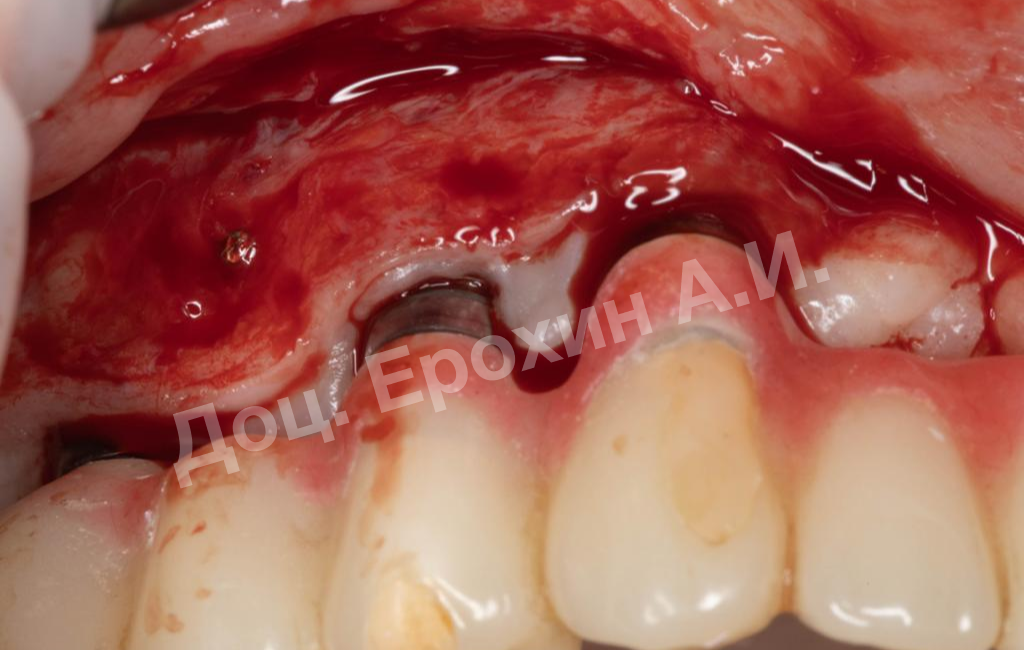

В результате, спустя 10 лет мы видим, что единственная часть десны в области имплантации, не затронутая рецессиями, — это зона, где была проведена трансплантация десневого фрагмента. С целью стабилизации имеющихся имплантатов на повторном приеме была проведена вестибулопластика по Кларку с фиксацией мягкотканных мукотомов, фрагментов эпителия с неба, зафиксированных швами.